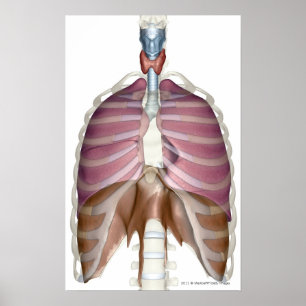

Hjärtans och lungornas struktur poster

Pris343,00 kr

Diagram över andningssystemet och hjärtat poster

Pris343,00 kr